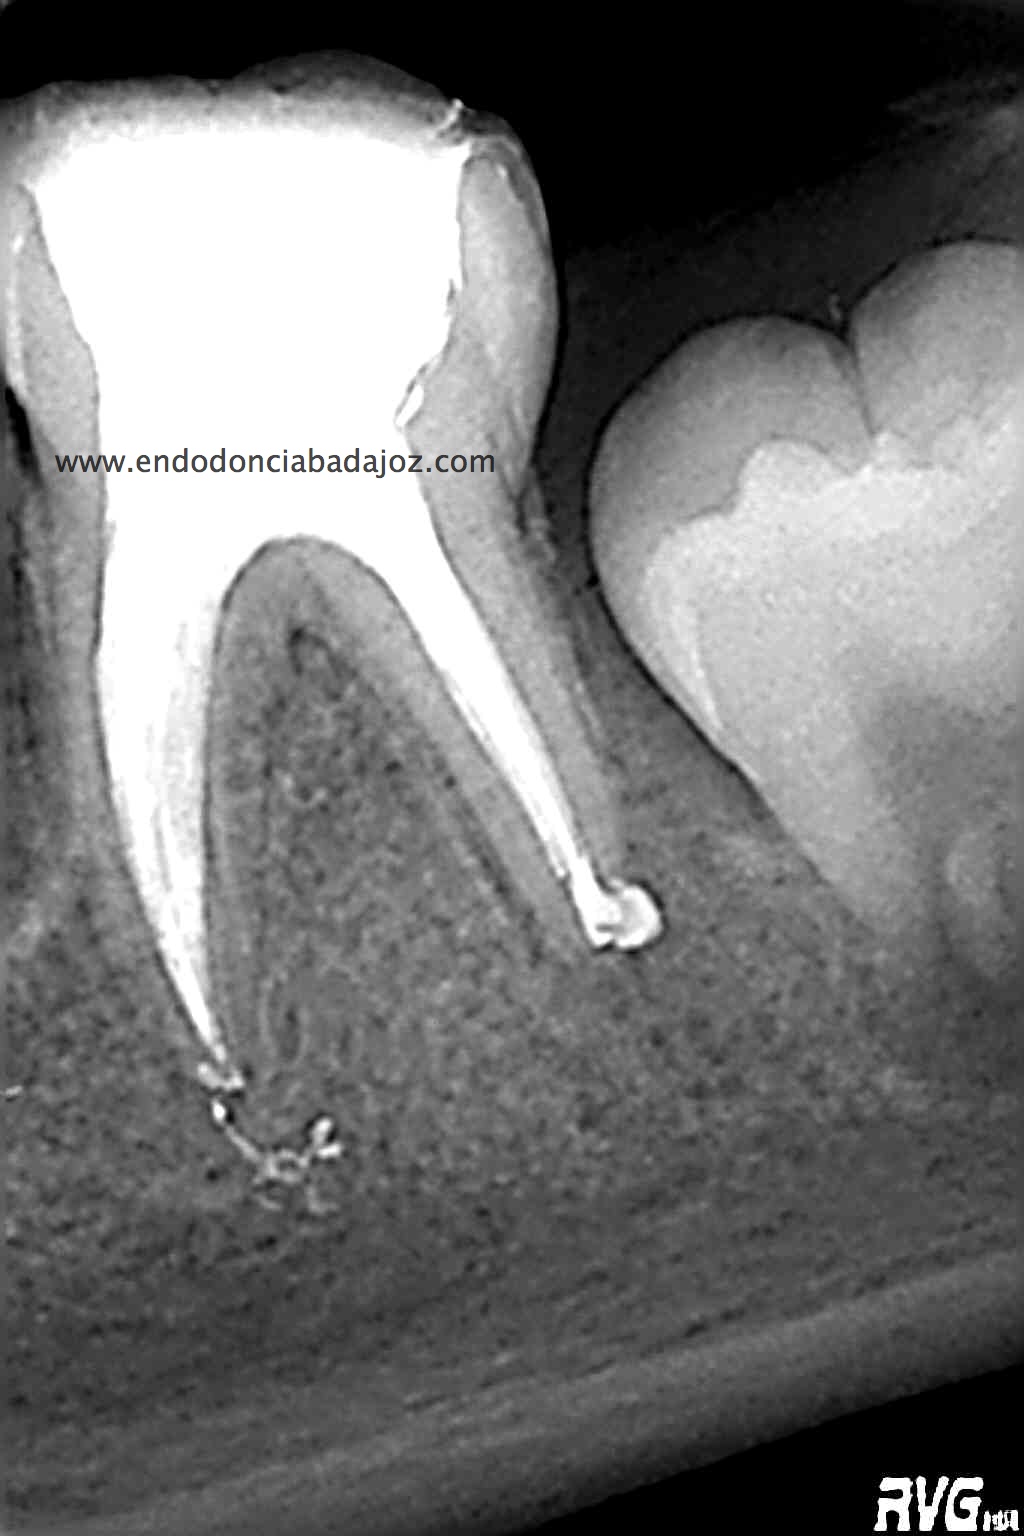

Esta última foto corresponde con un caso de un primer molar superior que la Rx no me esperaba que tuvieses tres conductos mesiales:

Son casos complicados, este en particular, por la ligera curva apical, que se agrava con la curva coronal, con lo que debemos aliviar modificando la apertura y acceso del tercio coronal con ultrasonidos e instrumentación.

Usamos los sistemas Pathfiles y las Mtwo, consiguiendo una buena preparación de los conductos

El sistema de obturación que usamos fue condensación vertical por ola de continua: